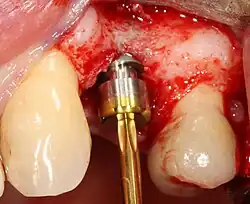

Основная операция по имплантации

Разборный имплантат состоит из непосредственно имплантата и надстройки (супраструктуры), именуемой абатментом. Такой имплантат может быть установлен по одно- и двухэтапному протоколу. Двухэтапный протокол подразумевает полное погружение имплантата и накрывание его слизистой оболочкой, в результате чего исключается любой контакт имплантата с полостью рта — эта процедура называется первым этапом дентальной имплантации. Второй этап заключается в установке какой-либо надстройки (супраструктуры) — это может быть как формирователь десны, так и абатмент с временной коронкой или другим видом протезной конструкции. После какого промежутка времени будет выполнен второй этап обычно решает имплантолог, опираясь на данные о качестве костной ткани, возраст и общее состояние пациента, а также свой клинический опыт. Классические сроки составляют 4—6 месяцев, однако последнее время существует тенденция к сокращению сроков ожидания до 2,5—3 месяцев. Это связано с лучшим пониманием процесса остеоинтеграции, а также оптимизацией макродизайна и микрохарактеристик поверхности имплантатов.

Внутрикостные имплантаты по форме разделяют на корневидные, пластиночные и комбинированные. Наибольшее распространение имеют корневидные имплантаты, которые могут быть цилиндрической или конической формы.

Корневидные имплантаты могут значительно отличаться по макродизайну резьбы: неагрессивная, агрессивная с глубокими полозьями, смешанные.